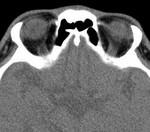

[画像診断]滑車の石灰化、上斜筋の走行について【後記研修医向け】 2011-05-11